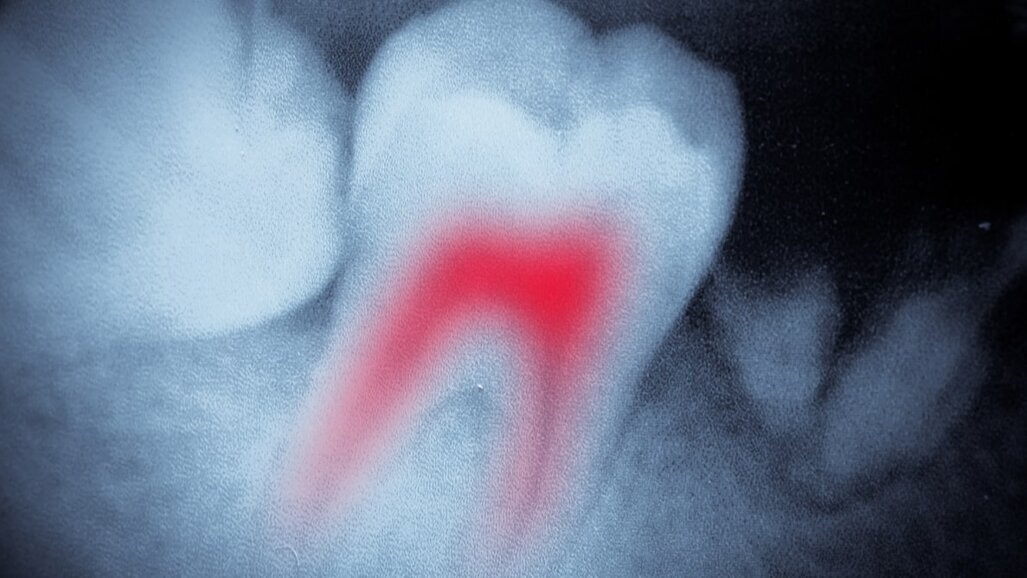

In Case 1, periapical periodontitis was diagnosed in tooth #37 after CBCT imaging in a patient aged approximately 50 years (Fig. 2). The mesial root canal entrances were difficult to identify because they contained welladapted, tooth-coloured composite. The treating endodontic specialist, Dr Thomas Rieger from Memmingen in Germany, selected the appropriate sequence of flexible NiTi files on Jeni’s touch screen. The HyFlex CM or EDM and the MicroMega One Curve or 2Shape from COLTENE are already pre-installed in the software. In the latest update, the 30/.07 HyFlex and MicroMega Remover files were added, making a significant difference to an endodontic revision treatment. The new Remover files fit perfectly with the established file systems and quickly and reliably remove inadequate gutta-percha fillings as well as similar endodontic restorations that have become outdated. In the Doctor’s Choice program, users can also store up to eight additional filing systems of their choice if they are familiar with the respective motion protocol.